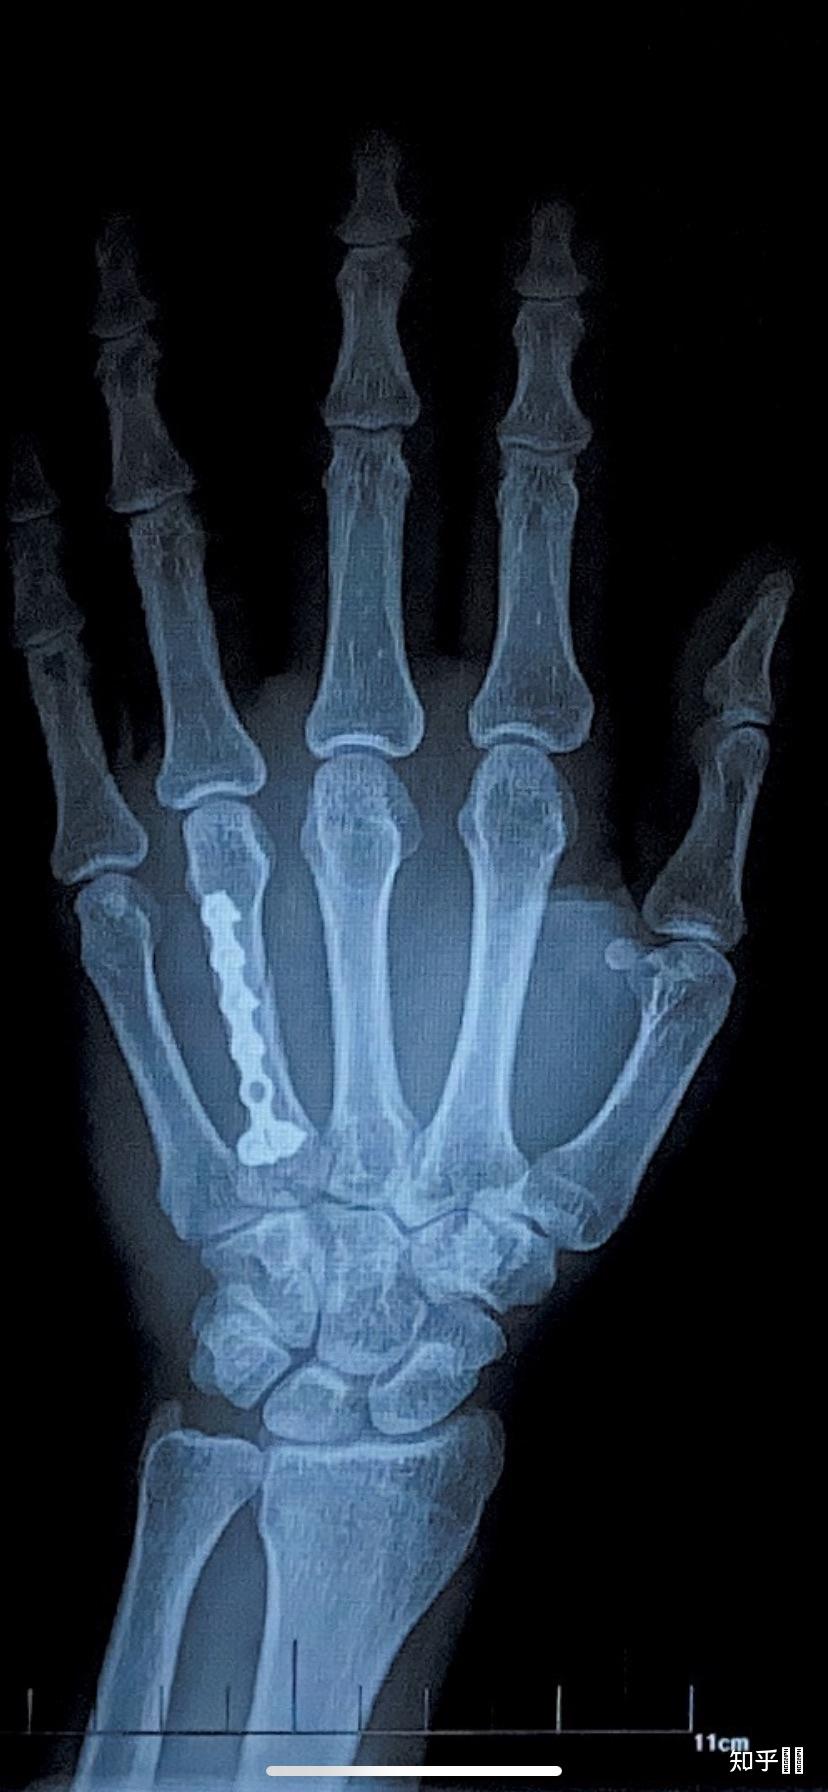

左手第四掌骨斜形错位骨折长好了

图片尺寸1080x1920